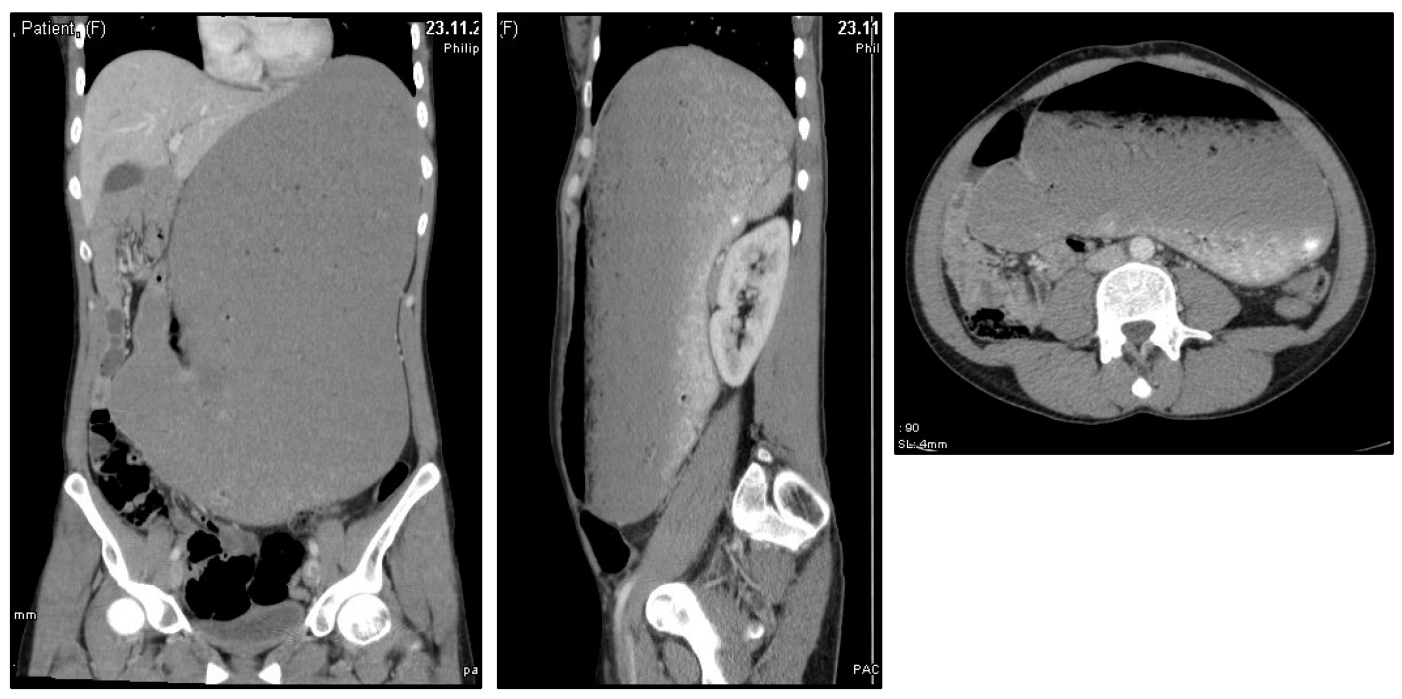

A 28-year-old woman presented in our surgical emergency unit with a sudden onset of progressive abdominal discomfort and pain. Anamnestically, the patient denied any preexisting conditions or previously performed surgeries. The patient was not under any long-term medication. Physical examination revealed a distended and meteoritic abdomen with signs of peritonism. Routine laboratory analysis did not show any pathologies, including normal hemoglobin, leucocytes, C-reactive protein (CRP) as well as serum electrolytes. Because of the acute and dramatic clinical presentation we immediately performed a computed tomography of the abdomen. This revealed a massively distended stomach with a cranio-caudal extension of 35 cm reaching the lesser pelvis, however, without evidence for perforation (Figure 1 [Fig. 1]). Initially, the cause for the distention remained elusive. The patients was admitted to our intensive care unit. A stomach tube was placed, which, however, did not drain any significant amount of stomach content. We therefore decided on an emergency explorative laparotomy on the same day. Intraoperatively, in addition to the massively dilatated stomach no abnormalities were detected. We performed a gastrotomy of the gastric antrum and recovered (over the period of one hour) a large amount of cementitiously clotted and undigested food scraps from the stomach. Subsequently, the stomach was closed by sutures and an intraabdominal drainage was placed. An intraoperative performed gastroscopy did not reveal any stenosis or other pathologies. The postoperative course was without complication. The stomach tube as well as the intrabdominal drainage could be removed within the first days after surgery. A gradual reintroduction of liquids was well tolerated. On the sixth postoperative day we performed a radiological imaging of the stomach using contrast medium which revealed a re-tonised stomach of a normal size without evidence for any stenosis (Figure 2 [Fig. 2]). Subsequently, the patient was allowed to normal food intake, which was well tolerated as well. The postoperatively initiated evaluation of the patient by a psychiatrist revealed that she had been suffering from an eating disorder since her childhood. This was initially characterized by an anorectic behavior with starvation und excessive exercising. Temporarily, her body mass index (BMI) had dropped to 11 kg/m². At consultation in our clinic her BMI was in the lower normal range. However, the patient reported on daily binge eatings caused by conflicts at her workplace. This had also occurred on the day of hospital admission, however on this day, the routinely self-induced vomiting after the binge attack failed. In a good status of health the patient could be dismissed from our clinic on the 13th postoperative day. The psychiatric co-treatment therapy was continued.

Figure 1: Computed tomography of the abdomen revealing a massively distended stomach Upon admission of the young woman presenting with the clinical picture of an acute abdomen, we performed a computed tomography of the abdomen. This revealed a massively distended stomach reaching the lesser pelvis.